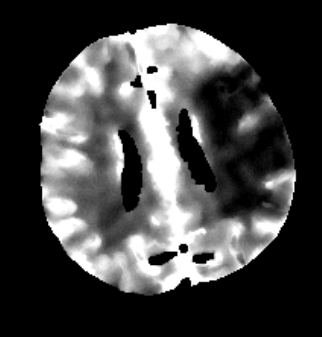

Furthermore mRay is capable of performing image processing tasks such as finding, visualizing and quantifying anomalies in tissue. In particular the image analysis module mRay VEOcore may be used to perform an automated processing of brain images from imaging modalities such as CT, CT-Perfusion, or MRI including a Diffusion Weighted Imaging (DWI) Module. As a result, changes in contrast over time are visualized as colored perfusion maps, including flow related parameters and tissue blood volume quantification.

The perfusion analysis of brain imaging data visualizes and quantifies tissue that is less supplied with blood (penumbra), oxygen deprived tissue caused by obstructed blood flow (core tissue) and the mismatch ratio between the two. The calculated values can be used to support decision making based on an assessment of the extent of tissue damage.

16.1. Overview

VEOcore is a fully automated image processing tool to calculate quantitative measures of affected brain tissue and healthy tissue. Therefore, this manual covers the instructions on how to interpret the results. It’s an extension the mRay Server application and the results can be viewed inside the mRay Client. Furthermore processed results can be automatically forwarded to the PACS.